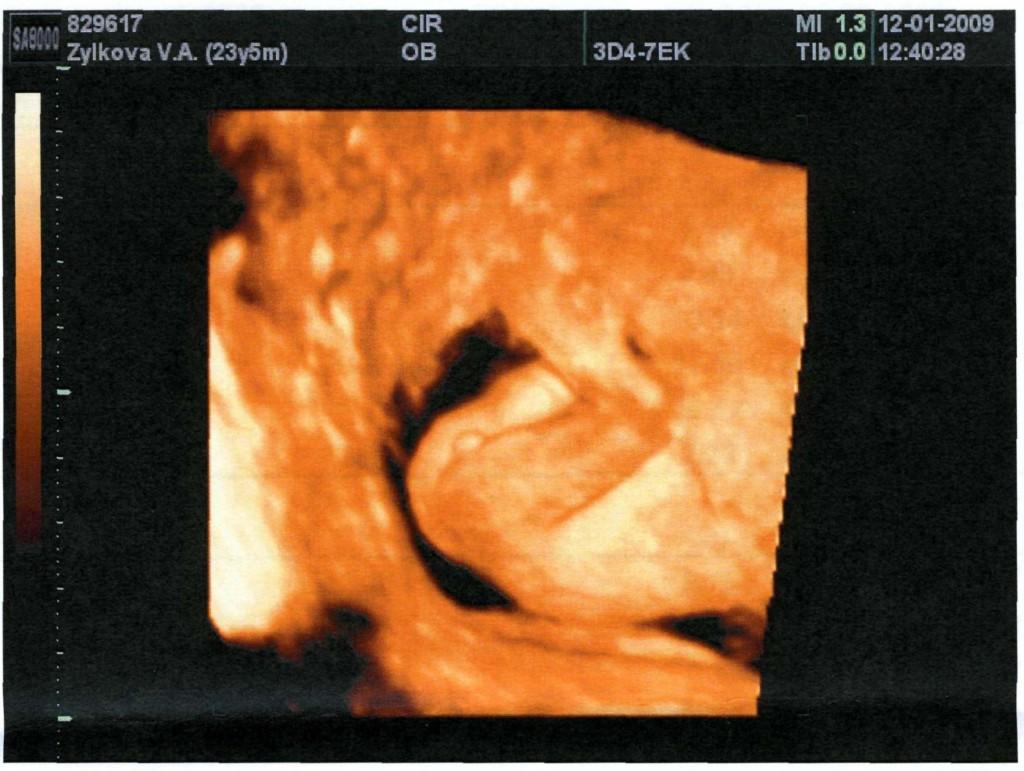

Рассмотрим фото мальчика на сроке гестации 5 месяцев. На снимке 4D видно, что пенис расположен под углом 30° к спинке ребенка.

- 3D-УЗИ (назначается с 24 недели беременности и показывает трехмерную картинку);

На ранней степени дифференцировки половые органы плодов обоих полов очень похожи, и их можно отличить друг от друга только с помощью аппаратуры с высокой степенью разрешения, например, 4D.